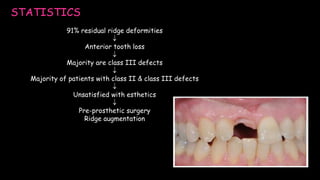

The document discusses pontic design for fixed dental prostheses. It covers pretreatment assessment of residual ridge contours, classifications of ridge deformities, surgical modification techniques, and ideal requirements for pontics. Pontic designs are classified based on their shape and materials. Factors in pontic selection include esthetics and oral hygiene. Common designs for anterior and posterior regions are described, including sanitary, ovate, and saddle pontics. Biological considerations for pontic design involve maintaining the residual ridge, abutment teeth, and supporting tissues.